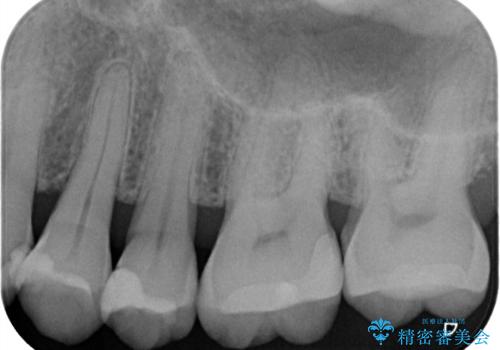

レントゲンで虫歯を発見 セラミックインレー

- 海外渡航前に、口腔内の悪いところを治しておきたいという患者様です。特に症状はない部位でしたが、レントゲンにて綿密にチェックしたところ、外側からは分かりにくい部分に虫歯が広がっているのを発見しました。隣の歯の金属も劣化しており、辺縁から感染を起こす恐れがあることが分かりました。一度の麻酔で一緒に治療が可能な範囲でしたので、2歯一緒にセラミック修復をいたしました。術後の経過も良好とのお電話を、わざわざ患者様からいただきました。

今回は、一度目に虫歯の除去と型どり、二度目にセラミック修復物のセットの計2回の治療で終了しています。一度目と二度目の間は、患者様には仮詰めを入れた状態で過ごしていただいております。